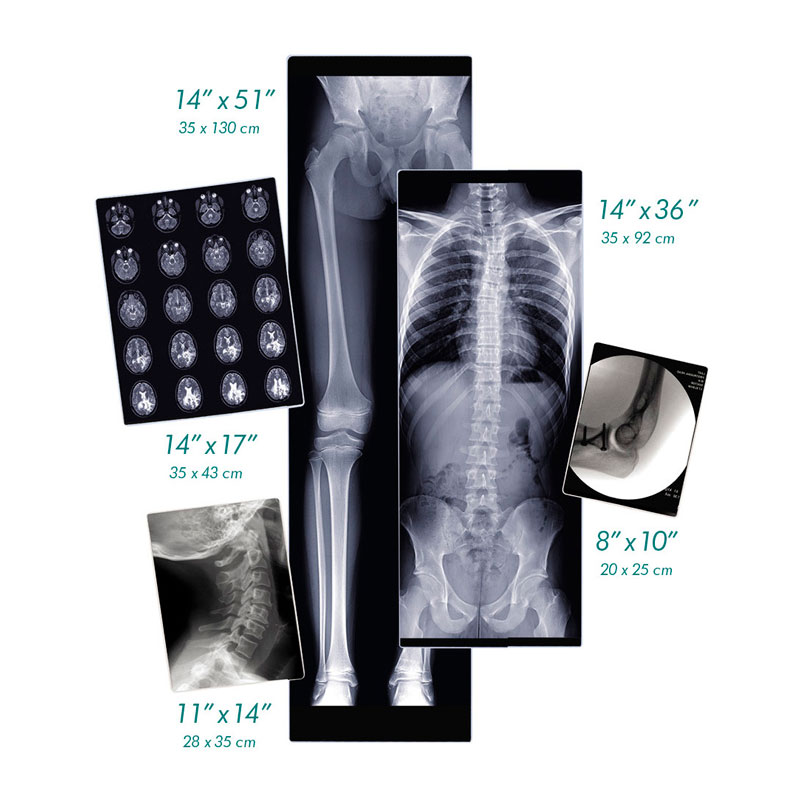

| Diagnostic Film | 14″x17″ 11″x14″ 8″x10″ 14″x36″ 14″x51″ |

- Only Horizon XL provides specialized orthopaedics with digital, dry film in 14″ x 36″ and 14″ x 51″ sizes ideal for long bone and scoliosis studies